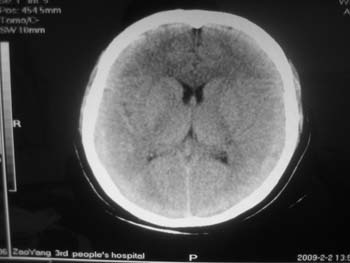

女。44岁,语言障碍三天,右侧上肢时而麻木。时而好转。其它图像未见异常。图像有点差请大家见谅。mg]/upload/forum/2009/02/0214453656449.jpg[/img]

蛛网膜囊肿

双侧额叶密度低,考虑线束老化或脑梗塞?

左侧枕叶脑软化灶?

双侧额叶脑梗塞,左侧枕叶脑软化灶,

临近脑沟五增宽,考虑蛛网膜囊肿